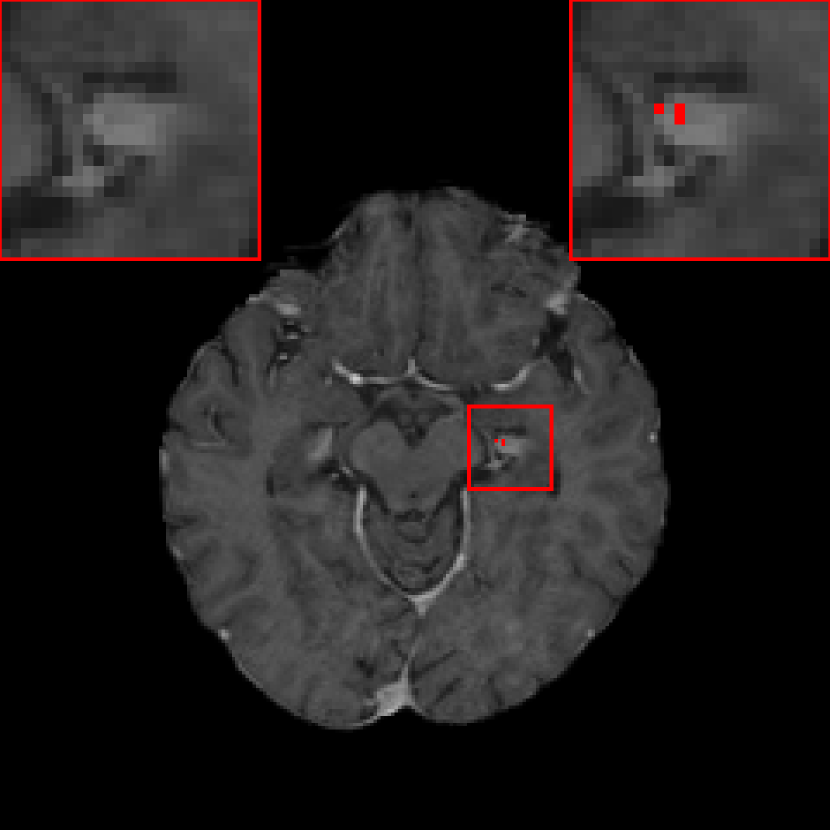

III.B. Results of DeepMedic+ using temporal prior

Fig. 5 is an example where temporal prior information is beneficial for metastasis identification. With an additional path for the prior volume, the red region in Fig. 5, as well as the other two cases in Fig. 5, is detected correctly. The sensitivity and precision for DeepMedic+ with the JVSS loss (α=0.995𝛼0.995\alpha=0.995 and α=0.5𝛼0.5\alpha=0.5) together with the temporal prior, i.e. senssubscriptsens\mathcal{M}_{\text{sens}} and specsubscriptspec\mathcal{M}_{\text{spec}} respectively, are displayed in Tab. 1. For α=0.995𝛼0.995\alpha=0.995 (senssubscriptsens\mathcal{M}_{\text{sens}}), the total number of FP metastases is reduced from 247 to 158, where 36.0%percent36.036.0\% ((247 - 158)/247) FP metastases are reduced. The average FP rate per patient is reduced from 2.40 (247/103) to 1.53 (158/103). As a trade-off, the sensitivity has a slight decrease from 0.946 (263/278) to 0.932 (259/278), with only 4 more FN metastases. Note that some of the test volumes are first scans without temporal prior volumes. If we exclude such volumes, the number of FP metastases decreases from 180 to 100 with the help of temporal prior, which is about 44.4% (180 - 100)/180 less, where 3 instead of 4 more FN metastases are observed. The average FP rate per patient is reduced from 2.54 (180/71) to 1.41 (100/71) for those with prior scans. For α=0.5𝛼0.5\alpha=0.5 (specsubscriptspec\mathcal{M}_{\text{spec}}), the sensitivity is slight worse than that of baselinesubscriptbaseline\mathcal{M}_{\text{baseline}}. However, the precision is as high as 0.996 (234/(234 + 1)) with only one FP metastasis. The FP case is displayed in Fig. 7, where the current main image together with its temporal prior and posterior images are displayed. The difference image between the main image and the temporal prior image is displayed in Fig. 7(c), where the area indicated by the arrow has larger difference. That is why specsubscriptspec\mathcal{M}_{\text{spec}} regards this region as a metastasis. However, after checking its posterior image (Fig. 7(d)), no grown metastasis exists. Therefore, we regard the detection in Fig. 7(b) as FP. But we cannot eliminate the possibility that a real metastasis has regressed at the segmented region before the posterior scan.

Refer to caption

(a) Prior image

(b) Main image with mask

(c) Difference ((b)-(a))

(d) Posterior image

Figure 7: The single false positive metastasis detected by specsubscriptspec\mathcal{M}_{\text{spec}}: (a) temporal prior image; (b) current main image, where the FP metastasis is marked by red color; (c) difference image ((b)-(a)); (d) temporal posterior image.